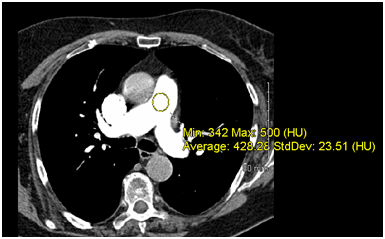

Signal intensity (attenuation) of pulmonary arteries was defined as the average CT numbers (in HU) measured by placing circular regions of interest (ROI’s) at different levels; main pulmonary artery (Figure 2) and a basal segmental artery. Image noise was defined as the mean of the standard deviations (SD or Std Dev) of the CT numbers of the pulmonary vessels measured. The background signal was defined as the CT number measured in the paraspinal muscles at the level of the main pulmonary artery (HU backgr).

Figure 2 Example of a calculation of Hounsfield Unit in a CTPA scan in the main pulmonary artery